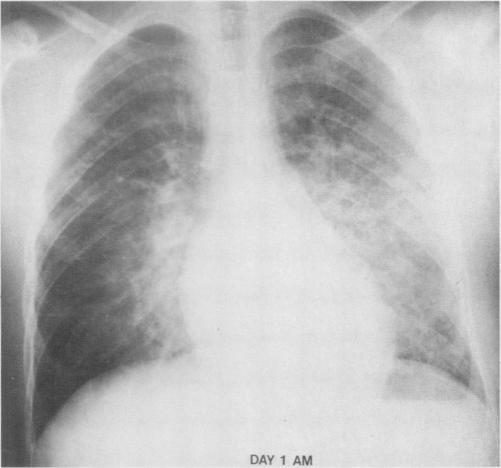

Nineteen cases of plague in Arizona. A spectrum including ecthyma gangrenosum due to plague and plague in pregnancy.

We review the cases of 19 successfully treated plague patients, with emphasis on the clinical and epidemiologic features of the disease. Proper staining and culturing of bubo aspirates; prompt institution of streptomycin, chloramphenicol or tetracycline therapy in presumptive cases, and supportive care are the crucial factors in the treatment of plague. This disease should be considered in patients in a toxic condition who have lymphadenitis, pneumonia or septic shock and who have been in endemic areas within the past ten days.